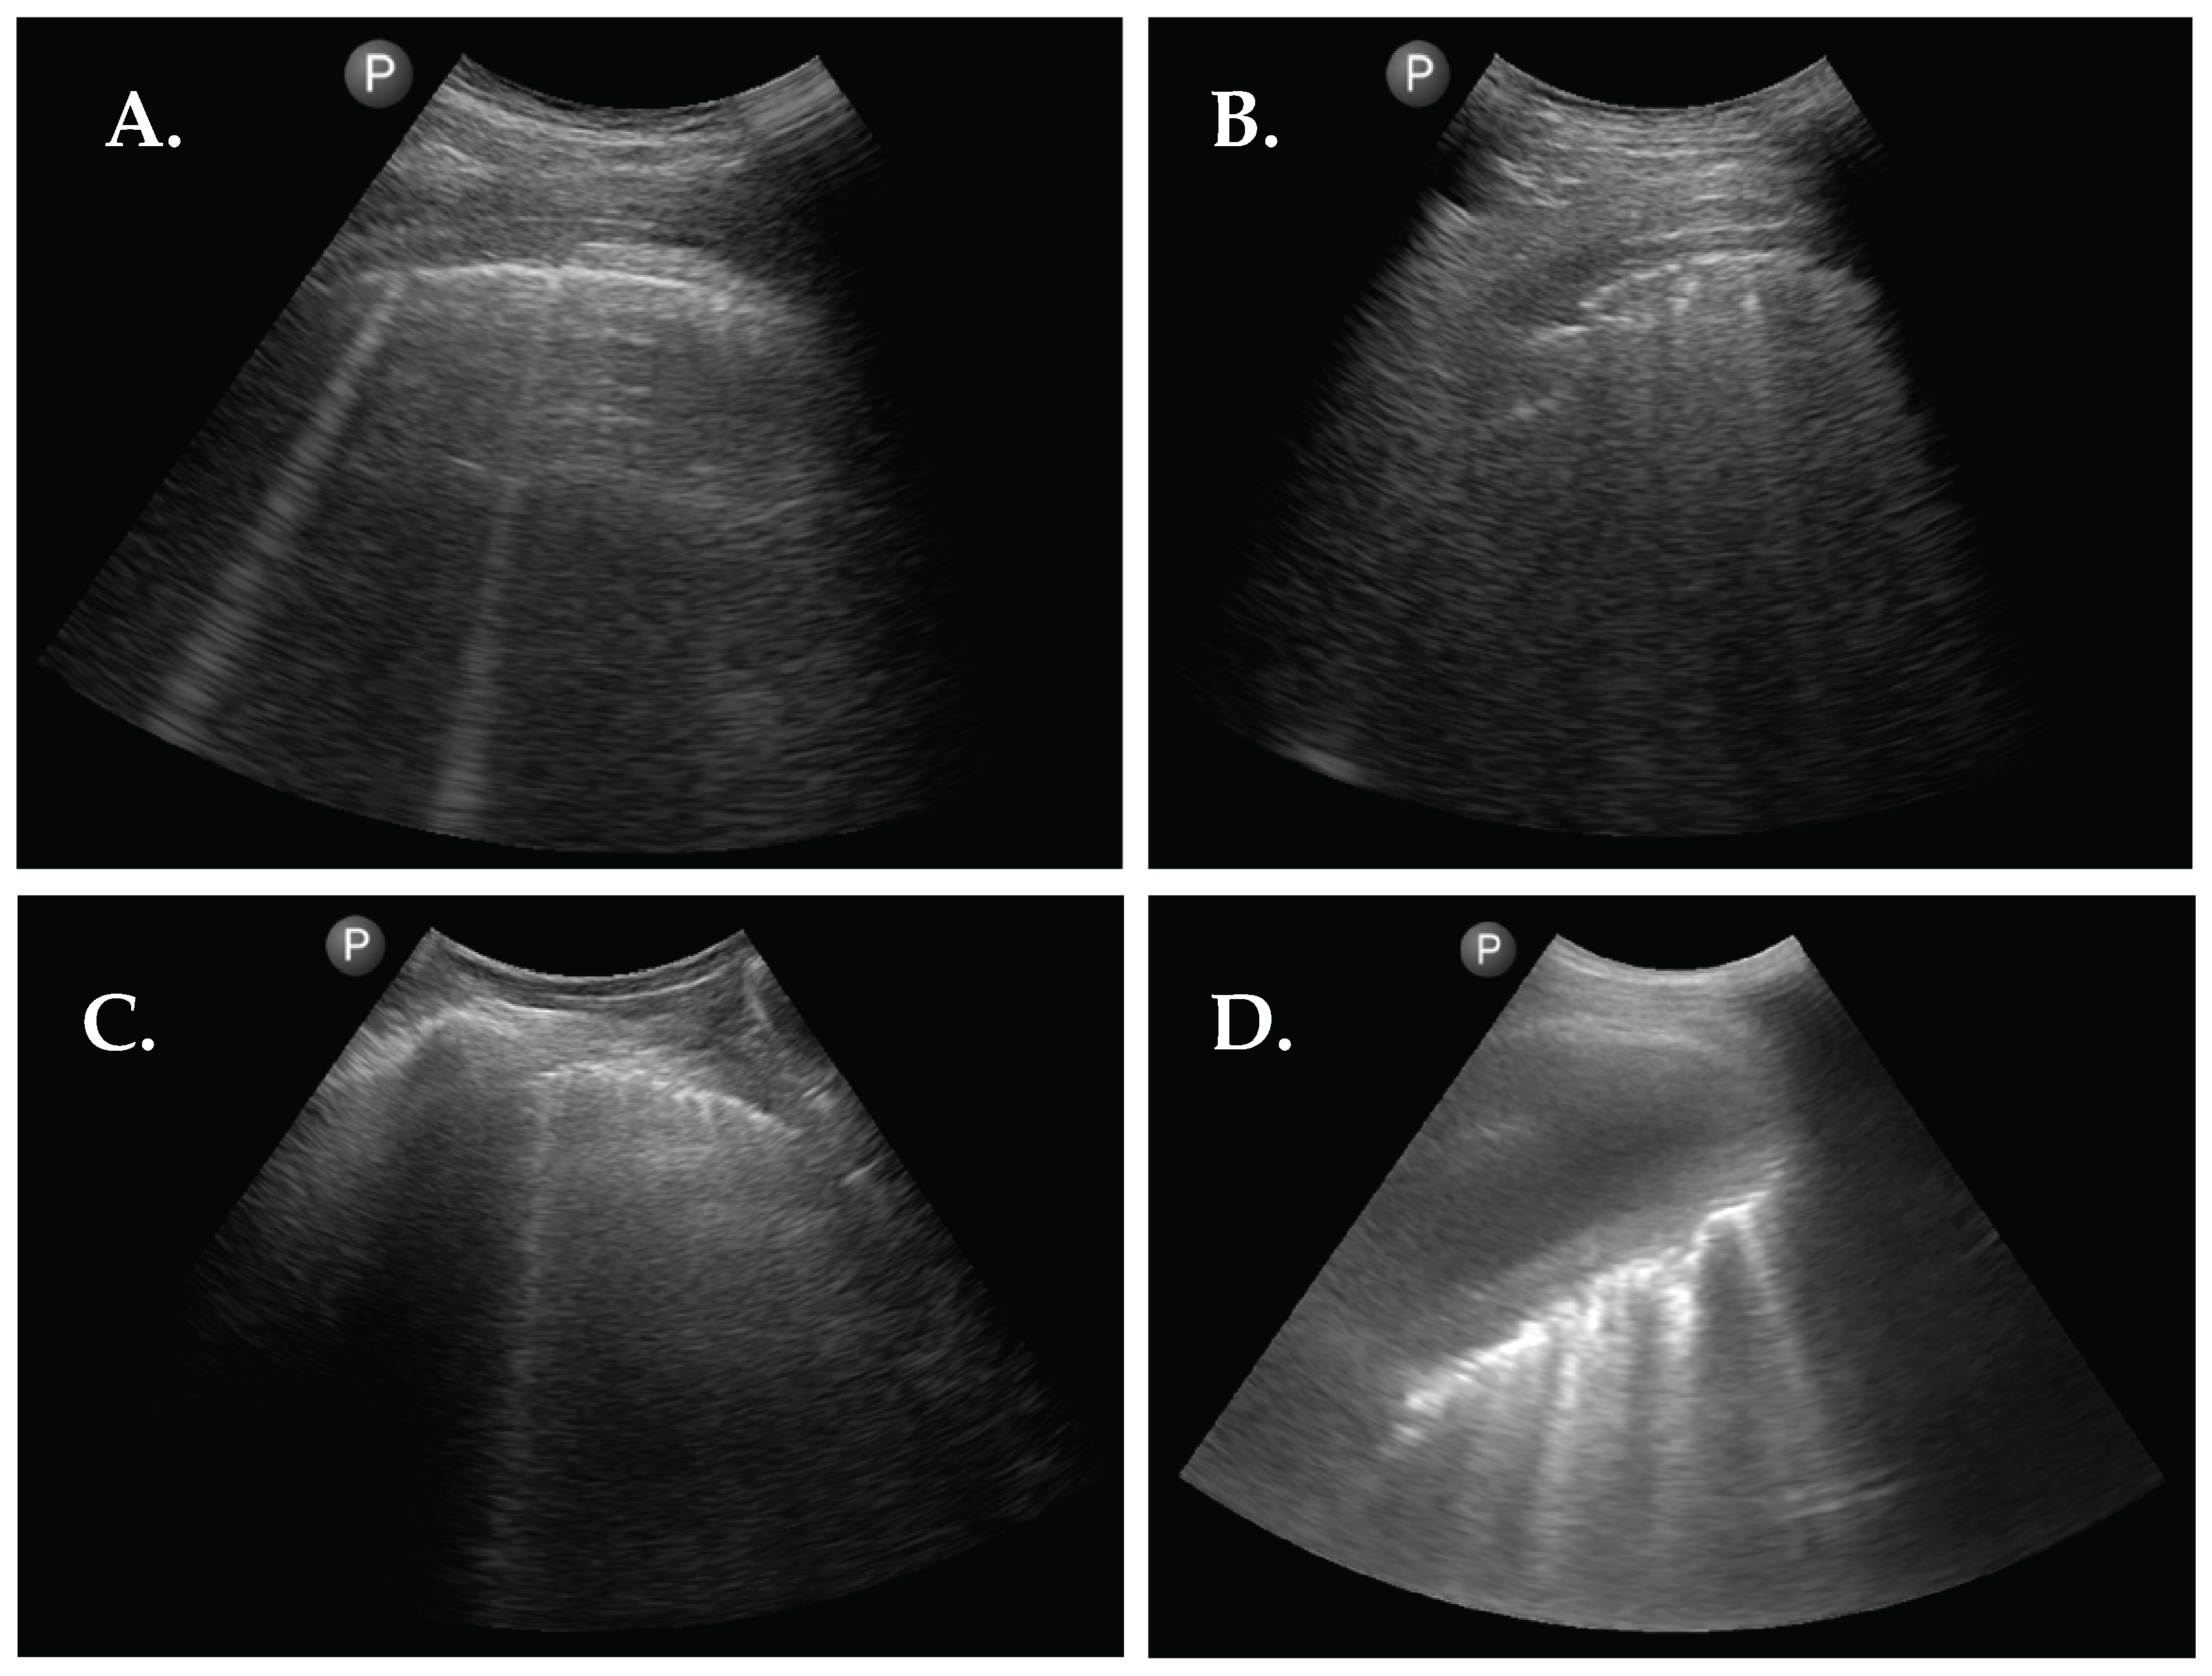

3.2. LUS Patterns